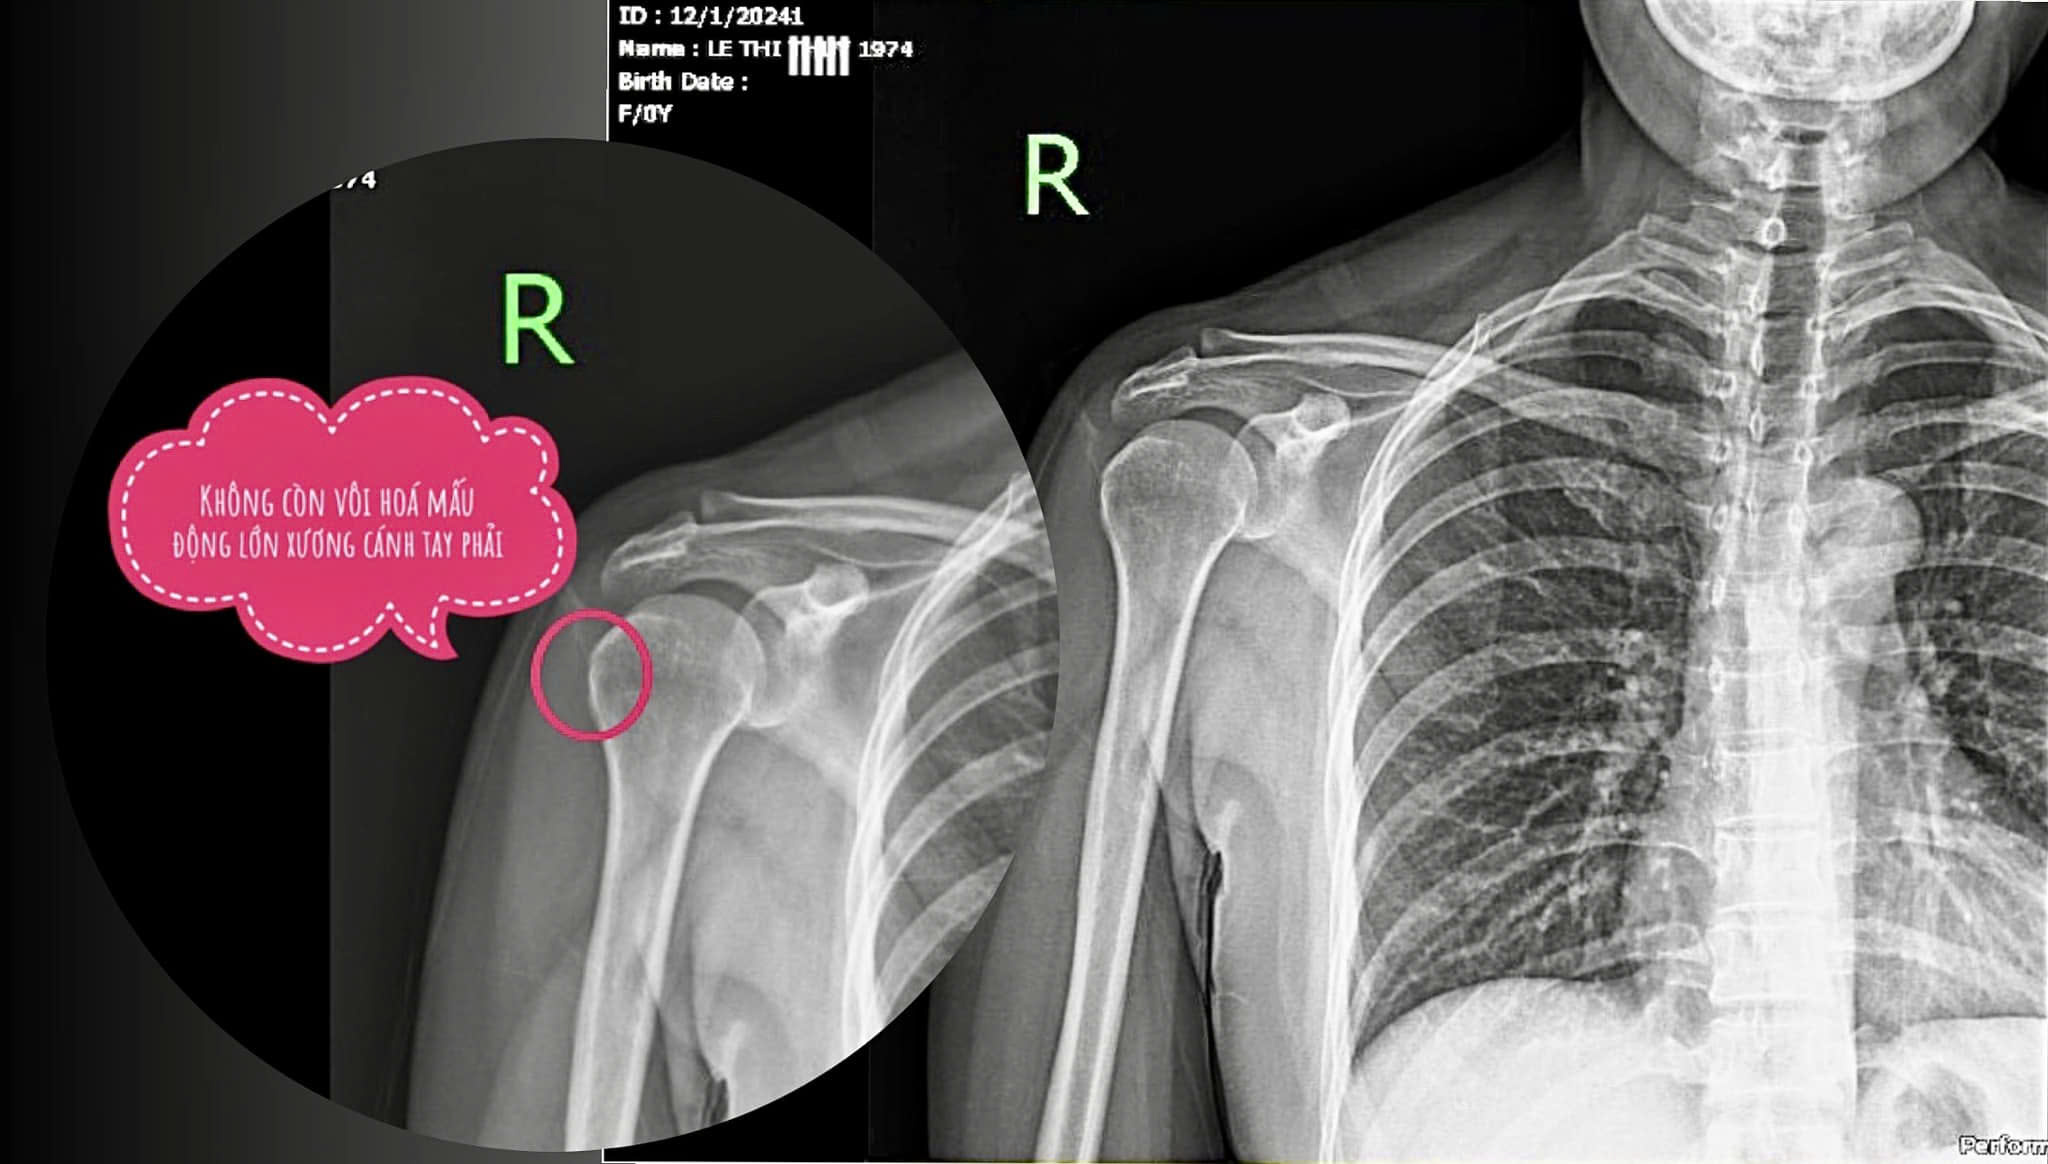

Kết quả siêu âm khớp vai: viêm gân nhị đầu dài, vôi hóa mấu động lớn xương cánh tay phải, viêm gân trên gai. Phim Xquang khớp vai thẳng, có vôi hóa mấu động lớn (Hình 3a).

Kết quả: Sau liệu trình trên tình trạng của bệnh nhân L.T.T đã cải thiện rõ rệt, không còn đau nhức, đêm ngủ, các sinh hạt hàng ngày như chải đầu, cài áo, làm việc sinh hoạt hàng ngày không bị đau lên, tầm vận động khớp vai trở về bình thường (dạng 180o- duỗi 45o- gấp 180o). Chụp Xquang đã tiêu hết điểm vôi hóa, sự thay đổi trước và sau điều trị thể hiện qua hình 3a, hình 3b.

Hình 3a: Bệnh nhân chụp phim trước khi điều trị

Hình 3b: Bệnh nhân chụp phim sau khi điều trị